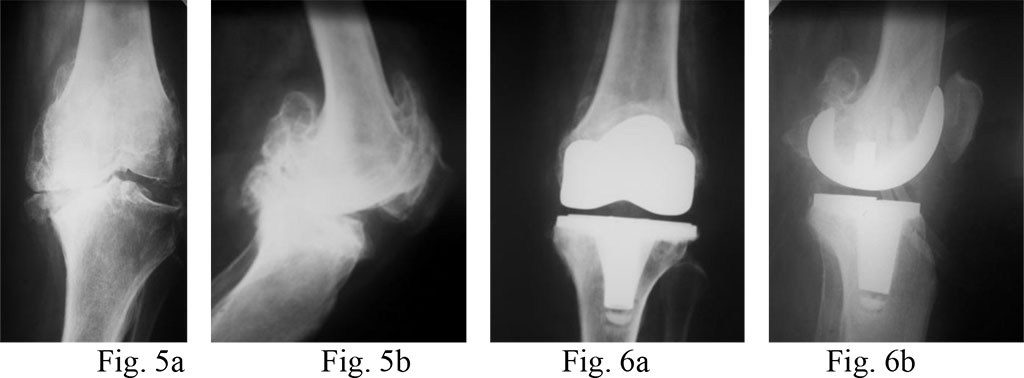

Diagnosis: knee osteoarthritis on the left, IV stage according to Kellgren&Lawrence; varus deformity of the joint, 15o flexion contracture of the left knee.

Surgical treatment: total arthroplasty of the left knee with an LPS prosthesis (without preservation of the PCL) (Fig. 5a, b and 6a, b)